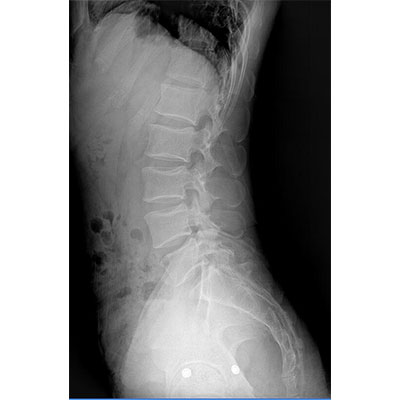

● 采用自主研發(fā)的技術(shù),在保證優(yōu)質(zhì)圖像的前提下,大大降低X射線(xiàn)劑量,用心呵護醫護工作者及患者的健康。

● 短曝光時(shí)間,便于老年人、兒童、殘疾人進(jìn)行臨床拍攝。避免這類(lèi)群體因不能有效控制身體運動(dòng)等因素造成的運動(dòng)偽影,提高攝片質(zhì)量及效率。